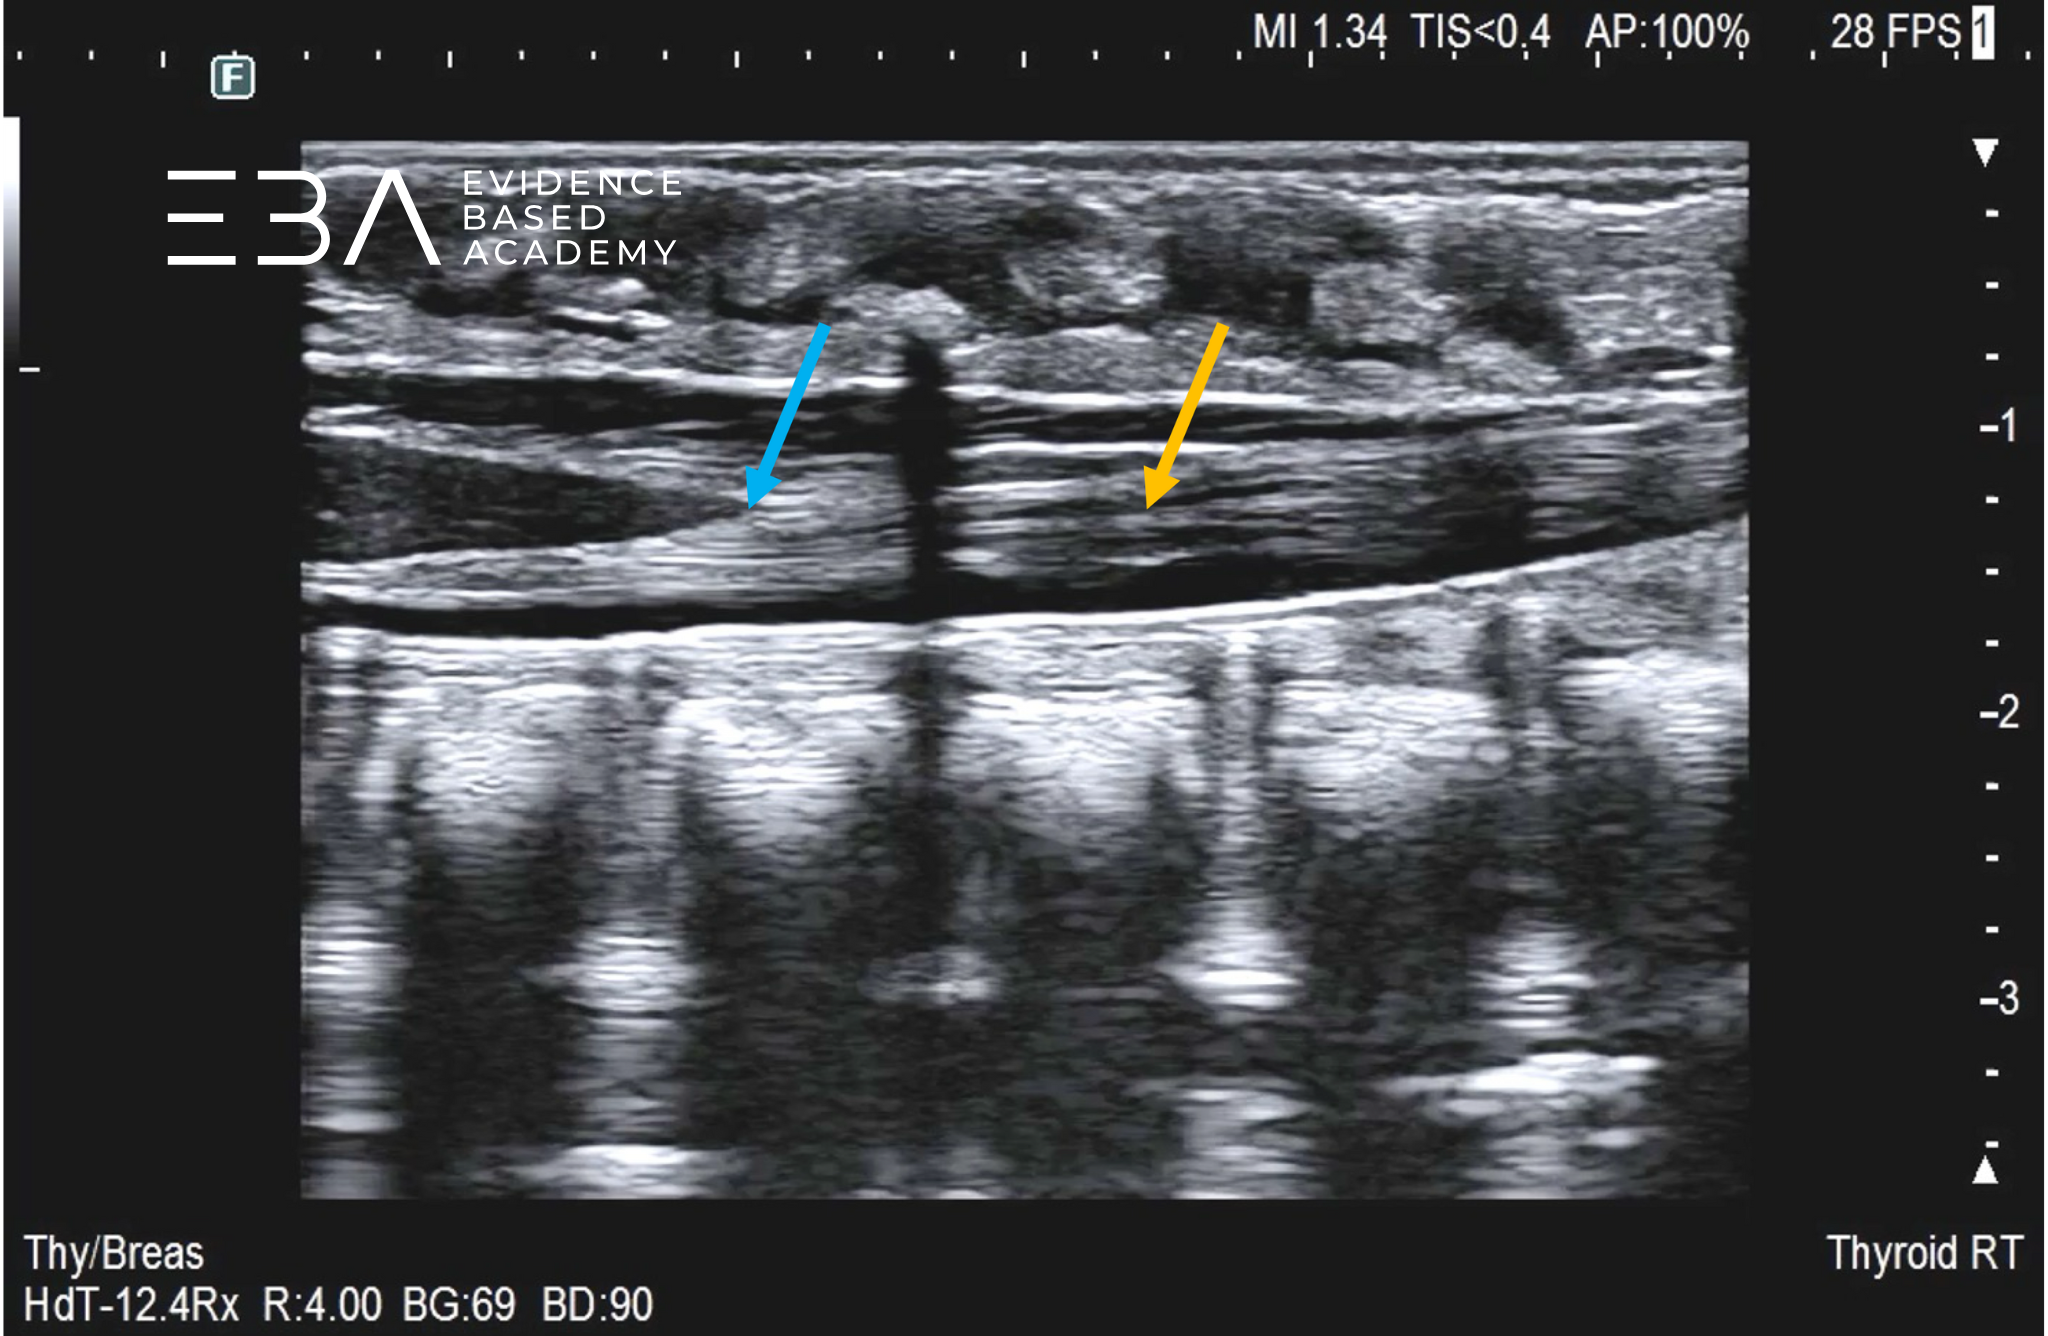

płaszczyźnie strzałkowej (podłużnej) rdzeń kręgowy jest widoczny jako hipoechogenna, tubularna struktura z centralnym echem odpowiadającym kanałowi centralnemu.

fot. 12

Kanał kręgowy, przekrój podłużny odcinka lędźwiowego i dalszej części odcinka piersiowego. Strzałką zaznaczono echo centralne rdzenia kręgowego (kanał centralny).

fot. 13

Kanał kręgowy, przekrój podłużny – widoczna różnica szerokości rdzenia w odcinku piersiowym (niebieska strzałka) i lędźwiowym (pomarańczowa strzałka).